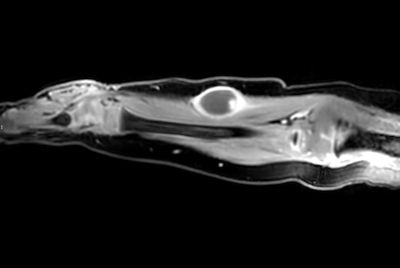

Pediatric forearm with lesion